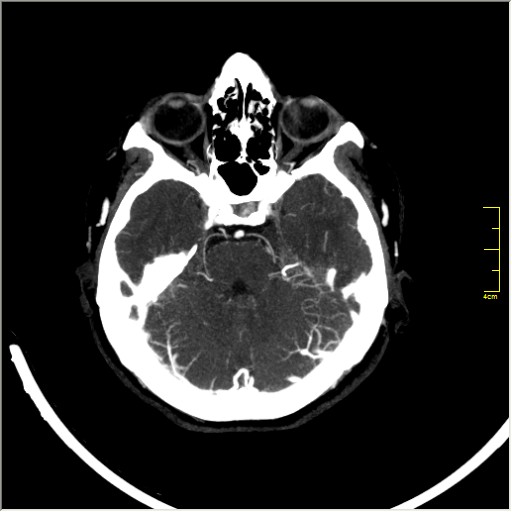

КТ ангиография головного мозга

Стандартная процедура в современной работе КТ кабинета, весьма несложна в исполнении.

Сканы представленны в режиме MIP.